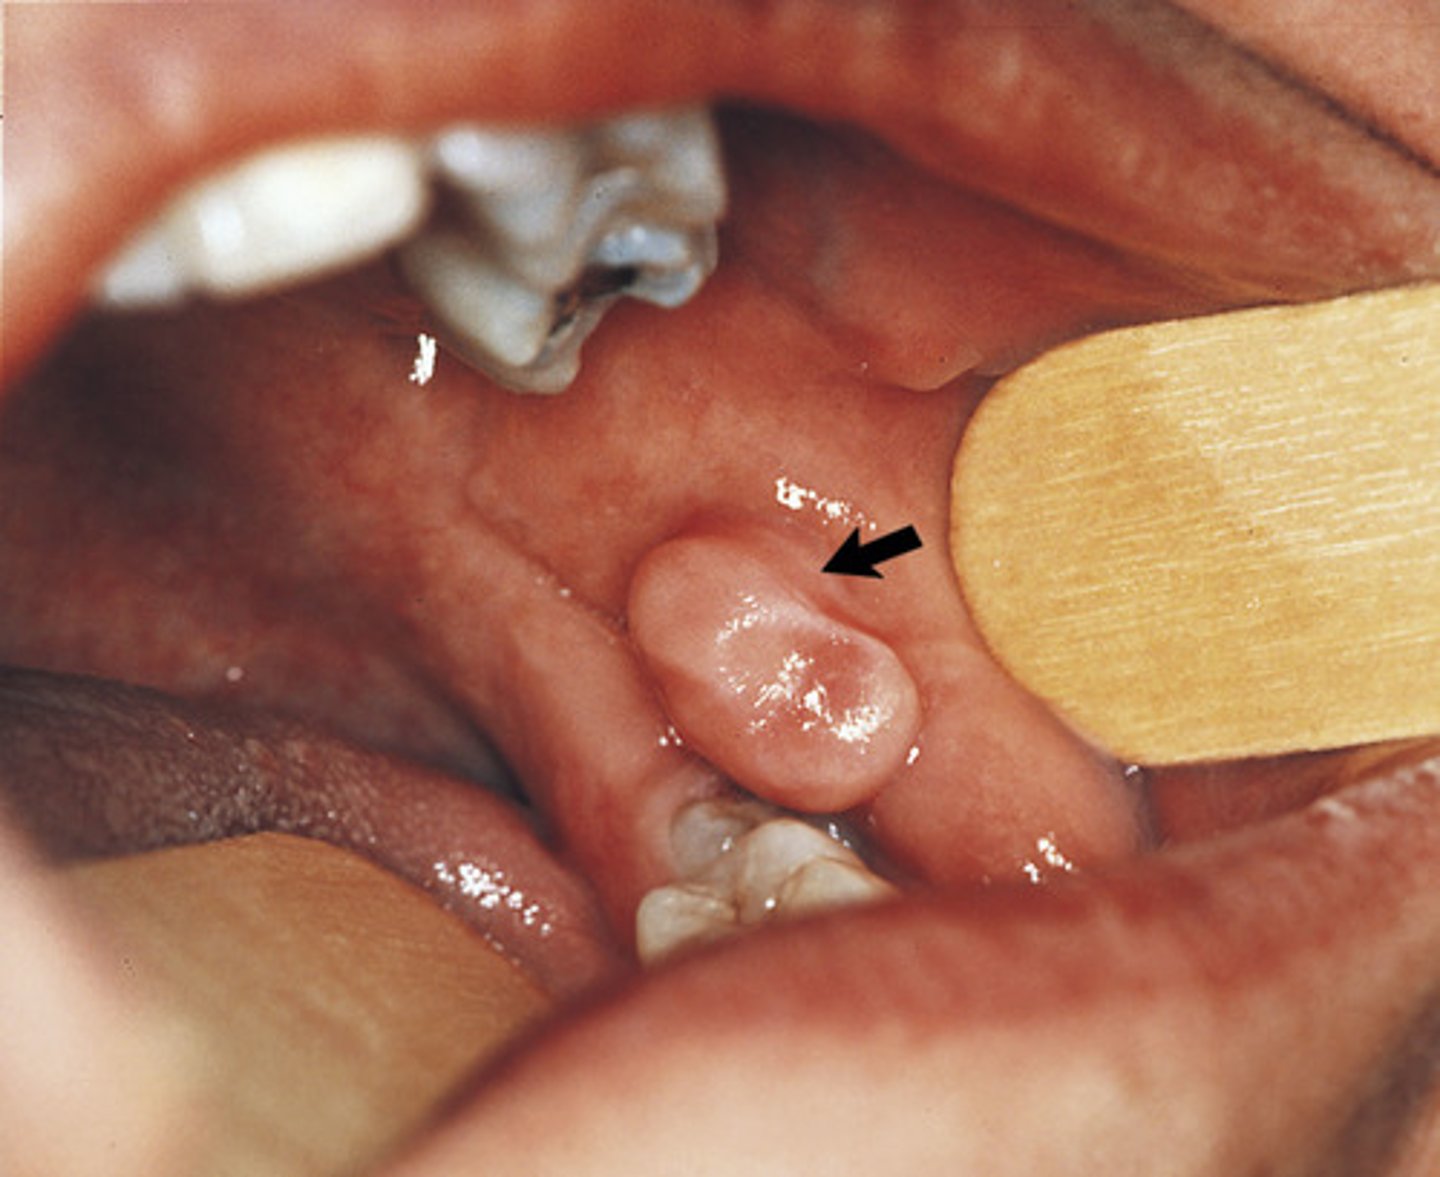

verrucous

The texture of this lesion would BEST be described as:

Pedunculated

The base of attachment for this lesion is: